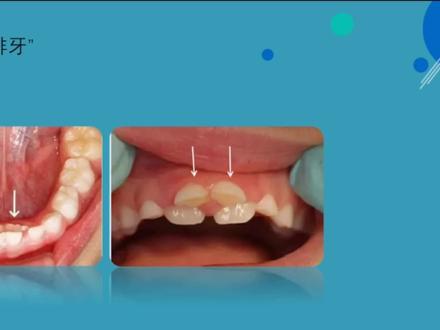

典型的双排牙分为两类,第一类是乳牙后面长出了新的牙齿,但乳牙仅仅轻微松动或者完全不松动。第二类是乳牙脱落后,恒牙没有在原来乳牙的位置,而是长在了旁边,形成了双排牙。双排牙的问题现在人力生长很常见,我们碰到每十个小朋友至少有五个存在 双排牙的问题。主要是恒牙萌出的过程中出现了障碍,每个乳牙根下方都对应一个恒牙胚,随着恒牙胚的慢慢萌出,令到乳牙根吸收逐渐松动、脱落,这就是换牙的过程。 出现双排牙的原因有两个,一个就是日常饮食过于精细,咀嚼得不到锻炼,却让恒牙萌出无力,乳牙根不吸收,导致乳牙不能脱落,而恒牙只能从滞留的乳牙旁边歪着长出来,形成了双排牙。第二,我们的牙齿就跟肌肉一样拥挤沸腾, 尤其是小朋友,在生长发育阶段更需要多锻炼。恒牙一般比乳牙大三分之一左右,如果不通过锻炼来促进合谷的正常发育,恒牙会因为没有足够的空间长得不整齐,甚至出现双排牙。 那么如何有效的预防双龅牙出现呢?主要是增加刺激。家长要循序渐进的给孩子吃一些硬度适中和撕咬的食物,比如可以给孩子啃个苹果、啃甘蔗、玉米、花生等耐咀嚼的食物。 这样做可以保持对乳牙良好的刺激作用,促进乳牙能够按时脱落。家长还应该监督孩子纠正孩子的不良习惯,比如咬唇咬舌、吹口哨、 小铅笔等等。其次,家长要让孩子培养良好的卫生习惯,定是好好刷牙,少吃甜食,少喝饮料,饭后刷牙漱口。那么孩子长 双排牙到底要不要拔呢?首先,我们家长朋友要先观察孩子口内乳牙数量是否正常,可以对照这个正常乳牙列表的图片数一下。其次,要连接正常的乳牙替换时间,比如下和中期牙,替换时间是六到七岁, 在正常替换时前后半年都是正常的。如果超过一年,就建议到专业的口腔诊所进行检查了。大家可以解读保存右边的儿童换牙顺序表,对照一下孩子的情况。最后,拔牙前要看恒牙萌出的高度,当恒牙只萌出三分之一或三分之二, 给前排牙齿还没有松动的情况下,建议家长要有耐心。如果放心,建议家长及时带孩子到医院进行诊治,切勿耽搁。

孩子刚刚换牙的时候,是不是有很多家长突然发现我的孩子怎么长了双排牙? 对,我今天就是要讲一下双排牙这个现象其实还挺常见的,尤其在我们的下倾牙啊,下倾牙在更换的时候,乳牙还没有脱落,恒牙又在他的后方给长出来了,变成了双排牙。 那双排牙的形成原因到底是什么呢?其实它主要是两个原因,第一个原因还是和我们的饮食习惯有关系 啊,以前的人出现的少,那是因为以前的人吃粗粮,吃这种不够精细的食物比较多,而我们现在的食物真的是太过惊喜了,都不需要孩子经过太多的咀嚼,所以呢,没有足够的咀嚼刺激传递到我们的 牙床,就是我们的颌骨上,我们底下的恒牙胚,他得不到刺激,我们的乳牙也得不到刺激,乳牙就不会正常的脱落,恒牙胚也不会正常的萌出。 所以第一个原因呢是我们的食物结构。第二个原因呢,就是我们的乳牙有一些出现了炎症取坏,他不够正常了,他和周围的软组织可能发生了一些粘连,牙根没有正常的去吸收,或者是呢,因为粘连他无法正常的脱落啊, 这种情况呢,也会导致我们的恒牙萌出,乳牙还没有掉落。那出现双排牙该怎么办?首先呢,当然是及早的去就诊,去找牙医就诊,检查一下我的乳牙是不是松动了,是不是该尽早的拔除给。 哎呀,咋新长出来的恒牙等萌出去挪位置呢?这一种是大部分的情况,还有一小类的情况呢,就是我们的恒牙萌出的还特别少,只有一点点尖,而乳牙呢,没有松动的特别厉害,这个时候还是可以观察个两周左右, 让孩子更多的去啃食物,比如说玉米啊,我们金州沙市的锅块对这种食物都是比较好的,去尽量的去拒绝,去啃,去刺激他,让乳牙尽快的松动。

孩子长了双排牙应该怎么办呢?双排牙形成的原因啊,就是因为食物吃的太过精细,苹果切小块吃,还经常吃软的面条啊,饼干啊,蛋糕啊,喝粥啊等等这些食物。 孩子呢颌骨没有发育,恒牙长出来,乳牙又没有退,影响孩子的剔牙。孩子嘴里啊就会出现双排牙。我建议大家到专业的口腔科去给孩子把滞留的乳牙给拔掉。 乳牙如果不拔的情况下呢,很容易造成恒牙的位置歪曲,最终会导致孩子牙齿里出外进的情况,后期的时候就需要做矫正了。